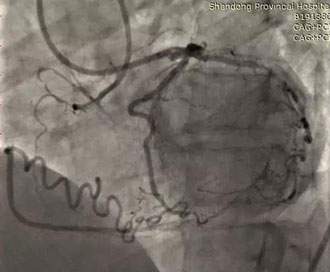

本例手术患者张某某,男,65岁,因“发作性胸闷胸痛9天入院”,曾当地行CAG检查示右冠脉CTO病变,遂转来我院治疗。经团队反复讨论后决定首先正向尝试,失败后则采用Stingray球囊辅助的ADR技术开通该右冠脉慢性完全闭塞病变。

图一:术前造影,示患者右冠状动脉近端闭塞,由LAD侧枝吻合向中远段供血